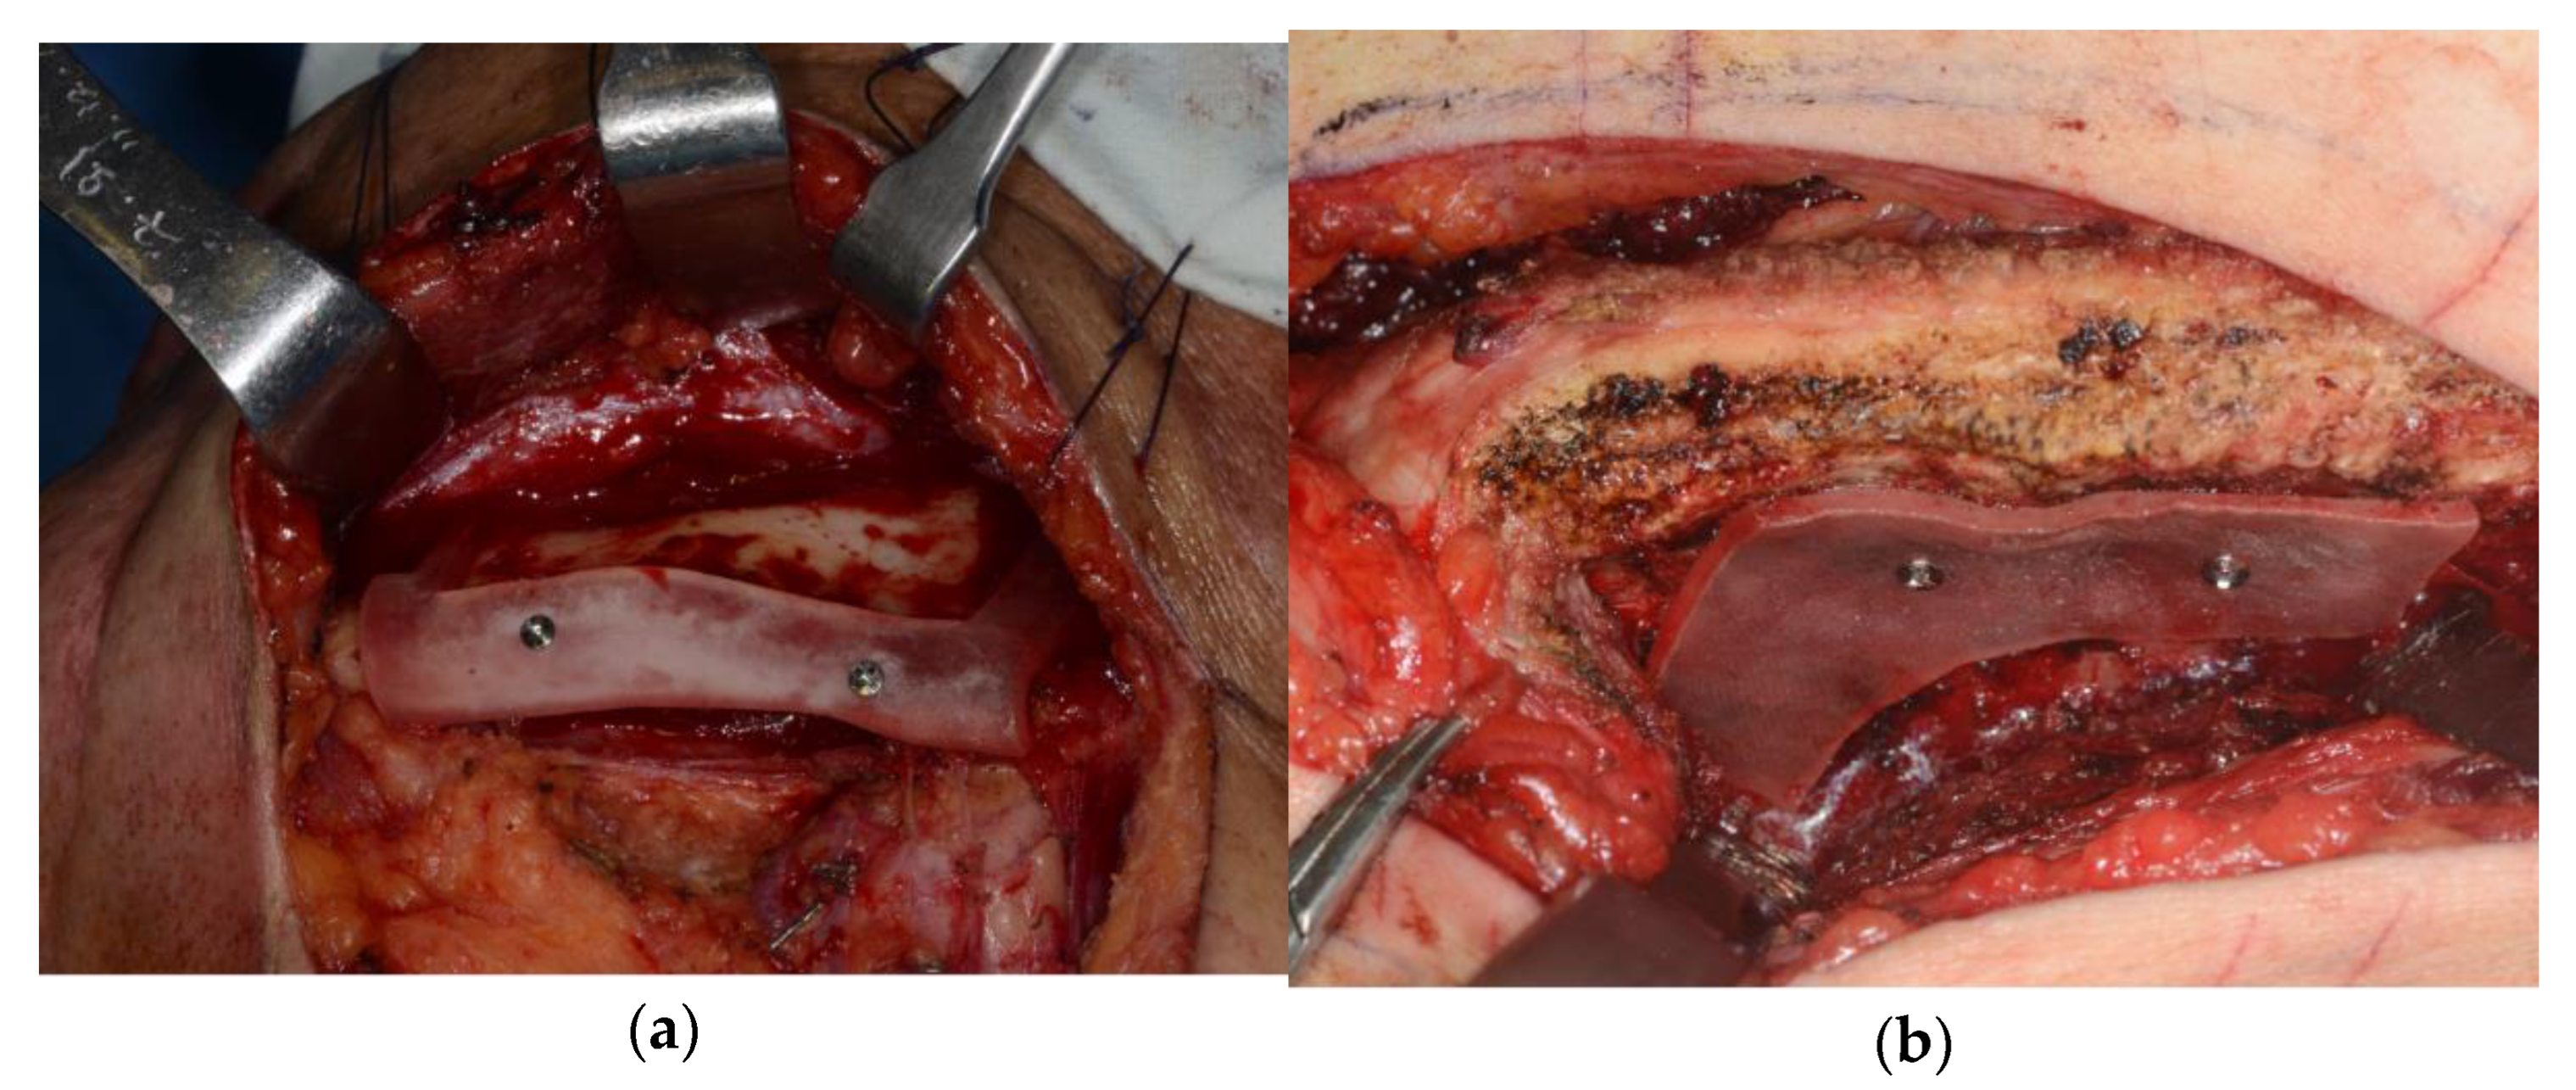

Open reduction of the fractured iliac crest bone was performed by applying a 3D-printed titanium implant to the external surface. A preformed 3D-printed porous titanium implant was inserted into the bone defect of the fractured iliac bone. The titanium implant was fixed to the iliac bone with 2.4 mm diameter screws through the pre-designed hole (Figure 3).

Figure 3.

(a) Intraoperative photograph; open reduction using customized titanium implant. (b) Postoperative iliac AP X-ray.

From 2 weeks postoperatively, the patient was able to stand and walk and was able to live without any discomfort for up to 1 year postoperatively. There was no recurrence of the primary tumor and no other complications were observed (Figure 4).

Figure 4.

Postoperative radiograph: (a) patient-specific implant shown on left iliac bone after 3 months; (b) well-reconstructed mandible after 4 months.